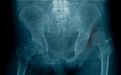

后脱位影像学:

股骨头较健侧缩小,股骨头与髋臼顶重叠;由于下肢内旋,小转子消失。

股骨头(橙色箭头)通常位于髋臼的上外侧,髋关节处于屈曲、内旋和内收状态。股骨内旋导致小转子明显性下降(黄色箭头)。注意本病例中有微小的髋臼后壁骨折(红色箭头)。